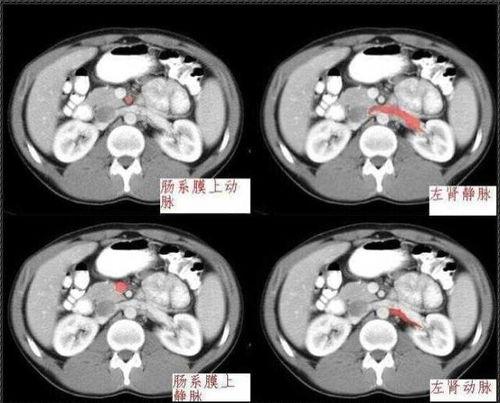

例如,一些视频会从腹壁开始,逐步深入到腹膜腔,展示胃、肠、肝脏、脾脏、肾脏等重要器官的位置和结构。有些视频还会通过动画效果,将器官的运作过程生动地展现出来,让我们仿佛置身于人体内部,亲眼见证生命的奇迹。